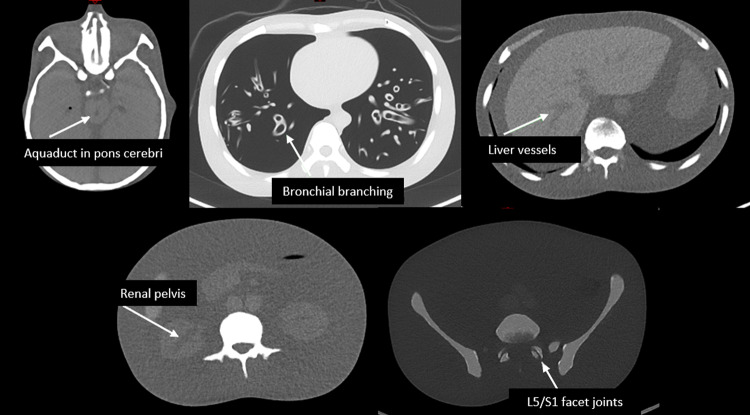

Materials and methods: A whole-body CT phantom was scanned with standard filtration in CRS protocols, using 120 kV with 20mAs-ref for bone L/C (used in 18F-Sodium Fluoride (NaF) PET-CT) and 40mAs-ref for soft tissue L/C (used in 18F-Fluorodeoxyglucose (FDG) PET-CT), followed by tin filter scans at 100 kV (Sn100kV) and 140 kV (Sn140kV) with a range of mAs settings. For each scan, effective dose (ED) in an equivalent-sized patient was calculated, and image quality determined in 5 different tissues through quantitative (contrast-to-noise ratio) and qualitative (visual) analyses. The relative dose reductions which could be achieved with the tin filter for comparable image quality to CRS images were calculated.